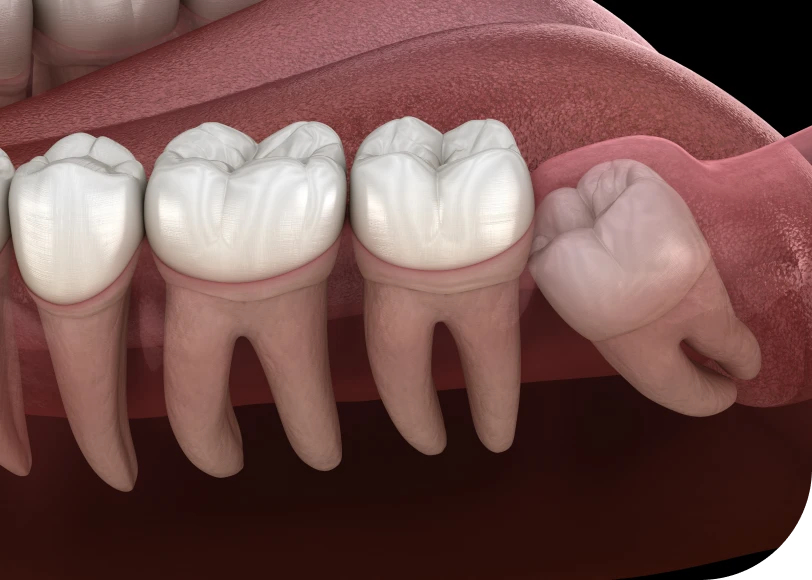

Extraire une dent incluse avec plus de précision

Lorsqu’une dent reste incluse (par exemple une dent de sagesse), son extraction présente un risque accru. Le guide chirurgical localise précisément la dent dans l’os. Ainsi, le praticien évite les dommages aux structures voisines, comme les nerfs ou les racines adjacentes.

De plus, il est possible de limiter la taille de l’ouverture osseuse. Cela rend l’intervention moins traumatisante.